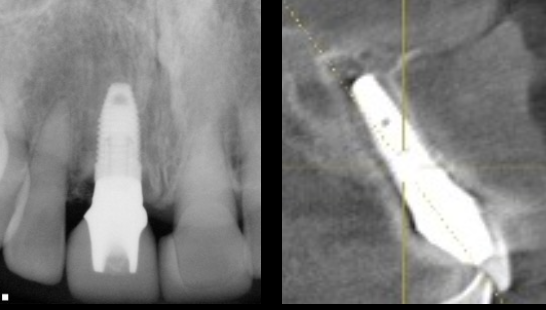

- 上顎右側前歯にインプラントを1本抜歯即時に埋入し、

- オールセラミックにて被せ物を行なった。

- 下顎左側臼歯に1本のインプラントを待時に埋入し、オールセラミッククランにて被せ物を行なった。

- 審美的な仕上がりで、患者自身も満足した。15年経過し良好である。

現在は2〜3ヶ月おきのメインテナンス中である。

インプラントの周囲は特に清掃が重要である。